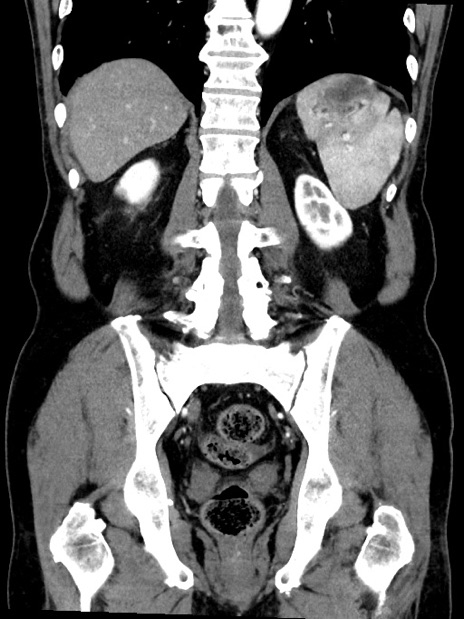

症例35(冠状断像)

【症例】70歳代 男性

【主訴】腹部膨満、嘔吐

【現病歴】昨日より腹部膨満感出現。本日増悪し、仙痛出現。嘔吐あり、受診。

【既往歴】糖尿病、胆摘後

【身体所見】BP 149/80mmHg、HR 74/min、BT 35.9℃、腹部:膨満、軟、圧痛なし。腸雑音減弱あり。上腹部正中切開瘢痕あり。

【データ】WBC 13500、CRP 1.72